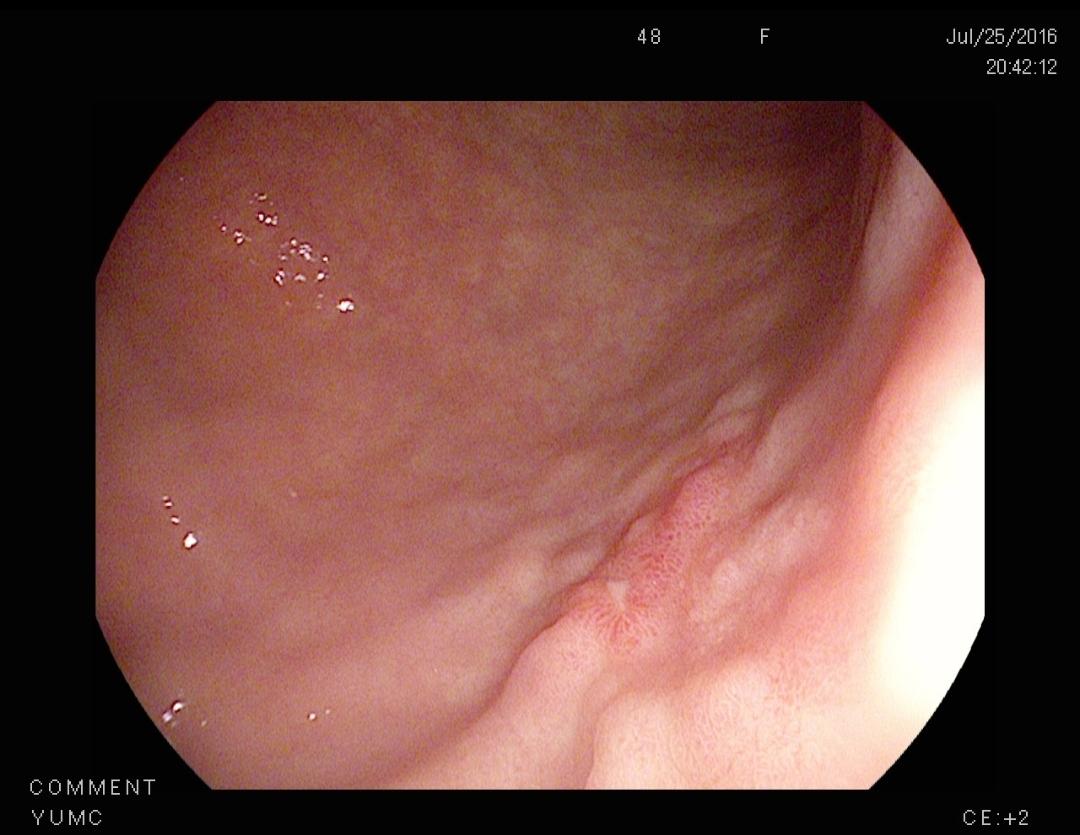

혹시 위암 판정 시 IHC를 통해 판정된 경우 초기일 가능성이 더 높아질까요? 내시경 cd 상으로 애매해서 재내시경 + 조직검사를 진행했고 IHC를 통해 위암 판정 받았습니다 궤양성으로 알고 있는데 혹시 이럴 경우 초기에 가까운지 여쭙고 싶습니다

IHC는 내시경 조직검사에서 일반 염색(H&E)만으로 암 여부가 애매할 때, 암세포의 성격을 보다 명확히 확인하기 위해 추가로 시행하는 보조적 진단 방법입니다. 즉 진단의 정확도를 높이기 위한 검사이지, 병기의 초기·진행 여부를 판단하는 기준은 아닙니다.

위암의 병기는 점막 또는 점막하층에 국한되어 있는지, 근육층 이상으로 침윤했는지, 림프절이나 원격 전이가 있는지에 따라 결정됩니다. 이는 내시경 소견, 조직검사 결과, CT 등 영상검사를 종합해 판단합니다. 궤양성 병변 역시 조기위암에서도 나타날 수 있고, 진행성 위암에서도 흔히 보이기 때문에 궤양이 있다는 점만으로 초기 여부를 단정할 수는 없습니다.